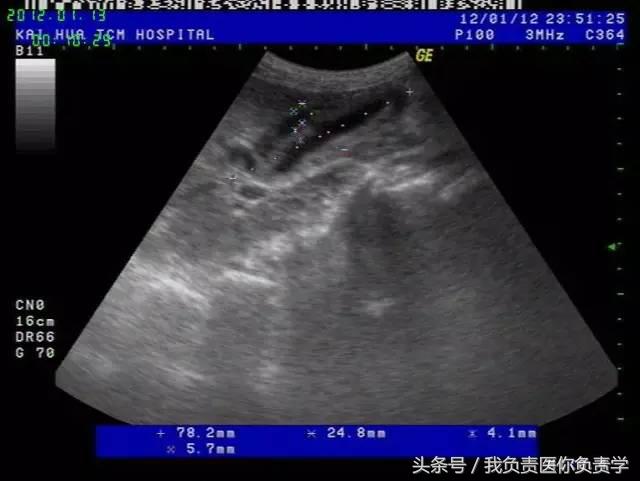

典型病例 2

(由丁香园注册用户「chengxiuyan_123」提供)

患者女,68岁,因上腹部痛 8天就诊 。超声检查发现胆囊体积明显增大,内部透声差,囊壁明显增厚,胆囊周围可见不规则分布的液性暗区。胆囊壁局部回声中断,探头加压及松开时,CDFI可见中断处出现因液体进出胆囊而导致的多普勒信号。患者行胆囊切除术,术后证实为胆囊穿孔。

图1示胆囊体积明显增大,内部透声差

图2示胆囊周围可见液性暗区分布

图3-图6示胆囊壁局部回声中断,探头加压及松开时CDFI可见红色及蓝色多普勒信号